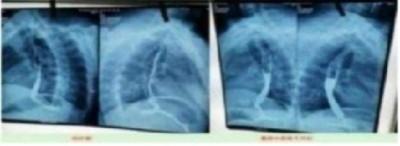

案例5右肺上叶癌(左侧颈部淋巴结转移、鳞状细胞癌)

患者岂六荣,53岁,系山西省晋中市左权县石匣乡管头村,于2013年1月9日前来就诊。因左胸憋闷,右肺呼吸困难,后背呈放射性疼痛近日加重。于2012年8月7日就诊于山西医科大学第一附属医院,行胸部CT示:右肺上叶癌,行气管镜示;右上叶后段支气管肺癌,右上叶支气管与右中间支气管分膌,右中间支气管开嗳累,病理回报:鳞状细胞癌(病理号12-12929)。于8月30日就诊于山西省肿瘤医院接受治疗。经该院各项检查最后诊断:右上叶癌:左侧颈部淋巴结转移,鳞状细胞癌,化疗后出院于2012年9月19日转山西武警总医院(第一次入院),2012年9月19日。住院期间经过完善的相关检查,期间出现血小板低下,给予升血小板治疗后,血小板恢复正常,后行伽玛刀治疗后,同时给予中药抗肿瘤药今患者及家属要求出院,于2012年10月10日家属要求出院,住院21天。出院诊断;1、右肺上叶癌2、左侧颈部淋巴结转移3、血小板低下,白细胞低下4、乙型肝类(恢复期)。第二次住院(2012年11月9日)出院(2012年11月21日)共住院12天。今患者及家属要求出院,于今日自动出院。

于2o13年1月8日一2o13年5月28日纯中药临床治愈,14o天清零。停药一年半后做医学鉴定:未见肿瘤细胞。至今11年未見复发,未見转移,不服药。一直从事农业劳动。于2024年2月10日(春节)上午10点接通岂六荣电话时,他正赶着羊群往后山上的路上,当我问到中午吃饭怎样解决时:因后山上离村有六七里山路,只有随干粮充饥,并告诉我每天上午10点准时出犮,下午4点半就回到家了。当我问到他身体时:"自从在您那里治好后十一年至今天,不复发,不服药。我很好,很健康,请陈大夫放心”。今天是过大年,你们早点回去,给您拜年,祝您全家新年快乐,平安,幸福!

国医楷模陈海林 | 癌细胞逆转正常生理细胞 引起全球广泛关注 —— 五一特别报道

岂六荣的癌症通过陈老师的高超技艺彻底治愈,前几天陈老师跟他通话他还在山上放羊,山上的温度很低大约在零下二十多度,在山上放羊,追逐羊群,没有好的身体根本不行。现在岂六荣的身体状态特别好,甚至比之前的身体还好。这就是中医药的魅力所在,伟大之处。